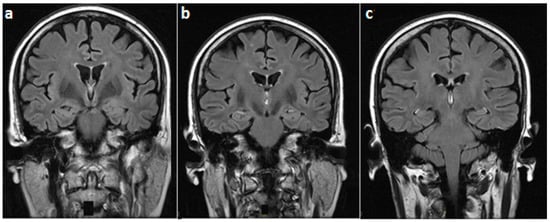

On examination, she was alert and cooperative, but disoriented to time and place, and unable to recall three objects on a mini-mental status exam. For the latter exam, the score was 18/30 on admission. Other cognitive domains were intact. In addition, cranial nerves as well as motor, sensory, and cerebellar functions were normal. The patient underwent brain MRI imaging which revealed normal T1, T2, and fluid-attenuated inversion recovery (FLAIR) sequences (Figure 1). However, T1 gadolinium-enhanced sequences demonstrated an isolated enhancement of the mammillary bodies (Figure 2).

Figure 2. T1-weighted gadolinium-enhanced MRI at the level of mammillary bodies (yellow arrows) ((a) coronal and (b) axial views) and (c) the third ventricle showing an isolated enhancement of the former.